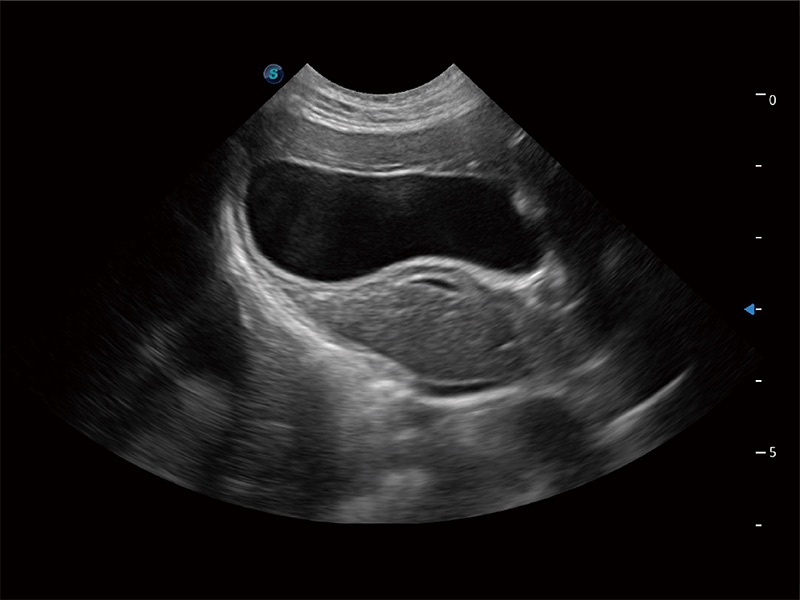

一鍵自動(dòng)識(shí)別膀胱壁及自動(dòng)測(cè)量膀胱容積,不受膀胱形狀和大小的限制,幫助醫(yī)生快速精準(zhǔn)獲得測(cè)量的數(shù)據(jù)。

為精細(xì)結(jié)構(gòu)及組織邊緣提供高清晰度的圖像和更大的成像視野。幫助減輕醫(yī)生的用眼疲勞,快速精準(zhǔn)獲得測(cè)量的數(shù)據(jù)。

ProPet 80 全新的動(dòng)物超聲智能軟件和豐富的探頭群,為動(dòng)物醫(yī)生提供了高清晰度和精細(xì)分辨率的圖像,無(wú)論在寵物、馬科、畜牧還是實(shí)驗(yàn)室動(dòng)物等應(yīng)用中都可以輕松應(yīng)對(duì),為您的日常工作帶來(lái)滿意的體驗(yàn)。